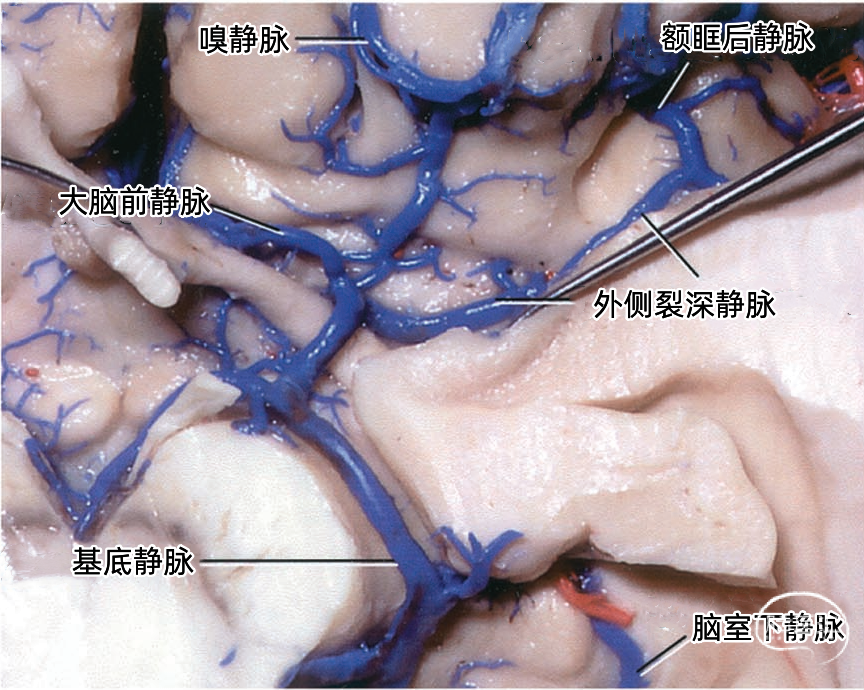

额叶的引流静脉分为外侧面组、内侧面组、底面组。外侧面组分为上升组,汇入上矢状窦;下降组,引流向外侧裂,进入外侧裂浅静脉。 上升组静脉包括额极、额前、额中、额后静脉,中央前静脉和中央沟静脉。这些静脉可能在回流至上矢状窦前与相邻的底面组、内侧面组的静脉汇合; 下降组由额外侧裂静脉组成。上升组引流的区域大于下降组。 额叶外侧面静脉及其引流区域如下:额极静脉引流额下回、额中回和额上回前部;额前、额中、额后静脉引流额极和中央前回之间的额叶前、中、后部凸面;中央前静脉引流中央前回下部、额下回盖部和邻近的额下、额中和额上回;中央Rolandic静脉引流中央沟附近的中央前回和中央后回;额外侧裂静脉引流额下回和邻近的额中回下部及中央前回下部。 额叶内侧面由弯曲的扣带沟分为内侧区和外侧区。额内侧静脉分为上升组进入上矢状窦;下降组进入下矢状窦或汇入行经胼胝体的静脉,最后进入基底静脉前端。上升组静脉由前内侧额静脉、中内侧额静脉、后内侧额静脉和旁中央沟静脉组成,它们是额上回内侧和邻近扣带回的主要静脉回流,一般向上弯曲走行,在半球上缘向外加入来自半球外侧组的静脉,然后注入上矢状窦。下降组静脉包括胼周前静脉、终板旁静脉和大脑前静脉。 额叶内侧面静脉及其引流区域如下:额前内侧静脉引流额极后方的扣带回和额上回;额中间内侧静脉引流胼胝体膝部前方的额上回和邻近扣带回的内侧面;额后内侧静脉引流胼胝体膝部上方的额上回和扣带回;旁中央静脉引流胼胝体体部上方的扣带回和邻近的旁中央小叶;胼周前静脉为成对的静脉,引流胼胝体膝部和嘴部,以及邻近的扣带回;大脑前静脉引流胼胝体嘴部以下至视交叉上缘之间的区域;终板旁静脉引流胼胝体嘴部下方的终板旁回和嗅旁回区域。 额下静脉组,引流额叶眶面区域,可分为前组和后组:前组流向额极注入上矢状窦;后组引流向后,在外侧裂内侧集中于前穿质表面,形成基底静脉。前组由额眶前静脉和额极静脉组成;后组由嗅静脉和额眶后静脉组成。 额下静脉及其引流区域如下:额眶前静脉引流直回前部和眶回前内侧部;额眶后静脉引流额叶眶面后部;嗅静脉引流嗅沟及其邻近的直回和内侧眶回。

嗅静脉、终板旁静脉、大脑前静脉和额眶后静脉汇合于基底静脉前端。

下图示左侧前穿质下方区域的放大观。嗅静脉、大脑前静脉、额眶后静脉、外侧裂深静脉汇集形成基底静脉。脑室下静脉在大脑脚后缘汇入基底静脉。